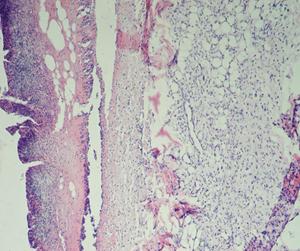

Раны характеризовались подрытыми, рубцово-фибринозными краями, вялыми и тусклыми грануляциями, с очагами некротических изменений, при гистологической оценке препаратов животных всех групп в области раны на 1-е сутки (4-е сутки с момента нанесения кожного дефекта) выявлено (рис. 15): поверхностно колонии микробов, некротизированная ткань, лейкоциты, детрит, фибрин. В подлежащих тканях выявляли: отек, плазматическое пропитывание, диффузно распределенные лейкоциты в подлежащей соединительной ткани.

Рис. 15. Крыса. 1-е сутки после инфицирования дефекта (4-е сутки от момента нанесения дефекта) А - ОГ; Б - КГ-1; В - КГ-2. 1 - некротизированная ткань, лейкоциты, детрит, фибрин; 2 - отек, плазматическое пропитывание, диффузно распределенные лейкоциты в подлежащей соединительной ткани. Окраска гематоксилином и эозином; А, Б, В (Об. 4х.; Ок. 10х).